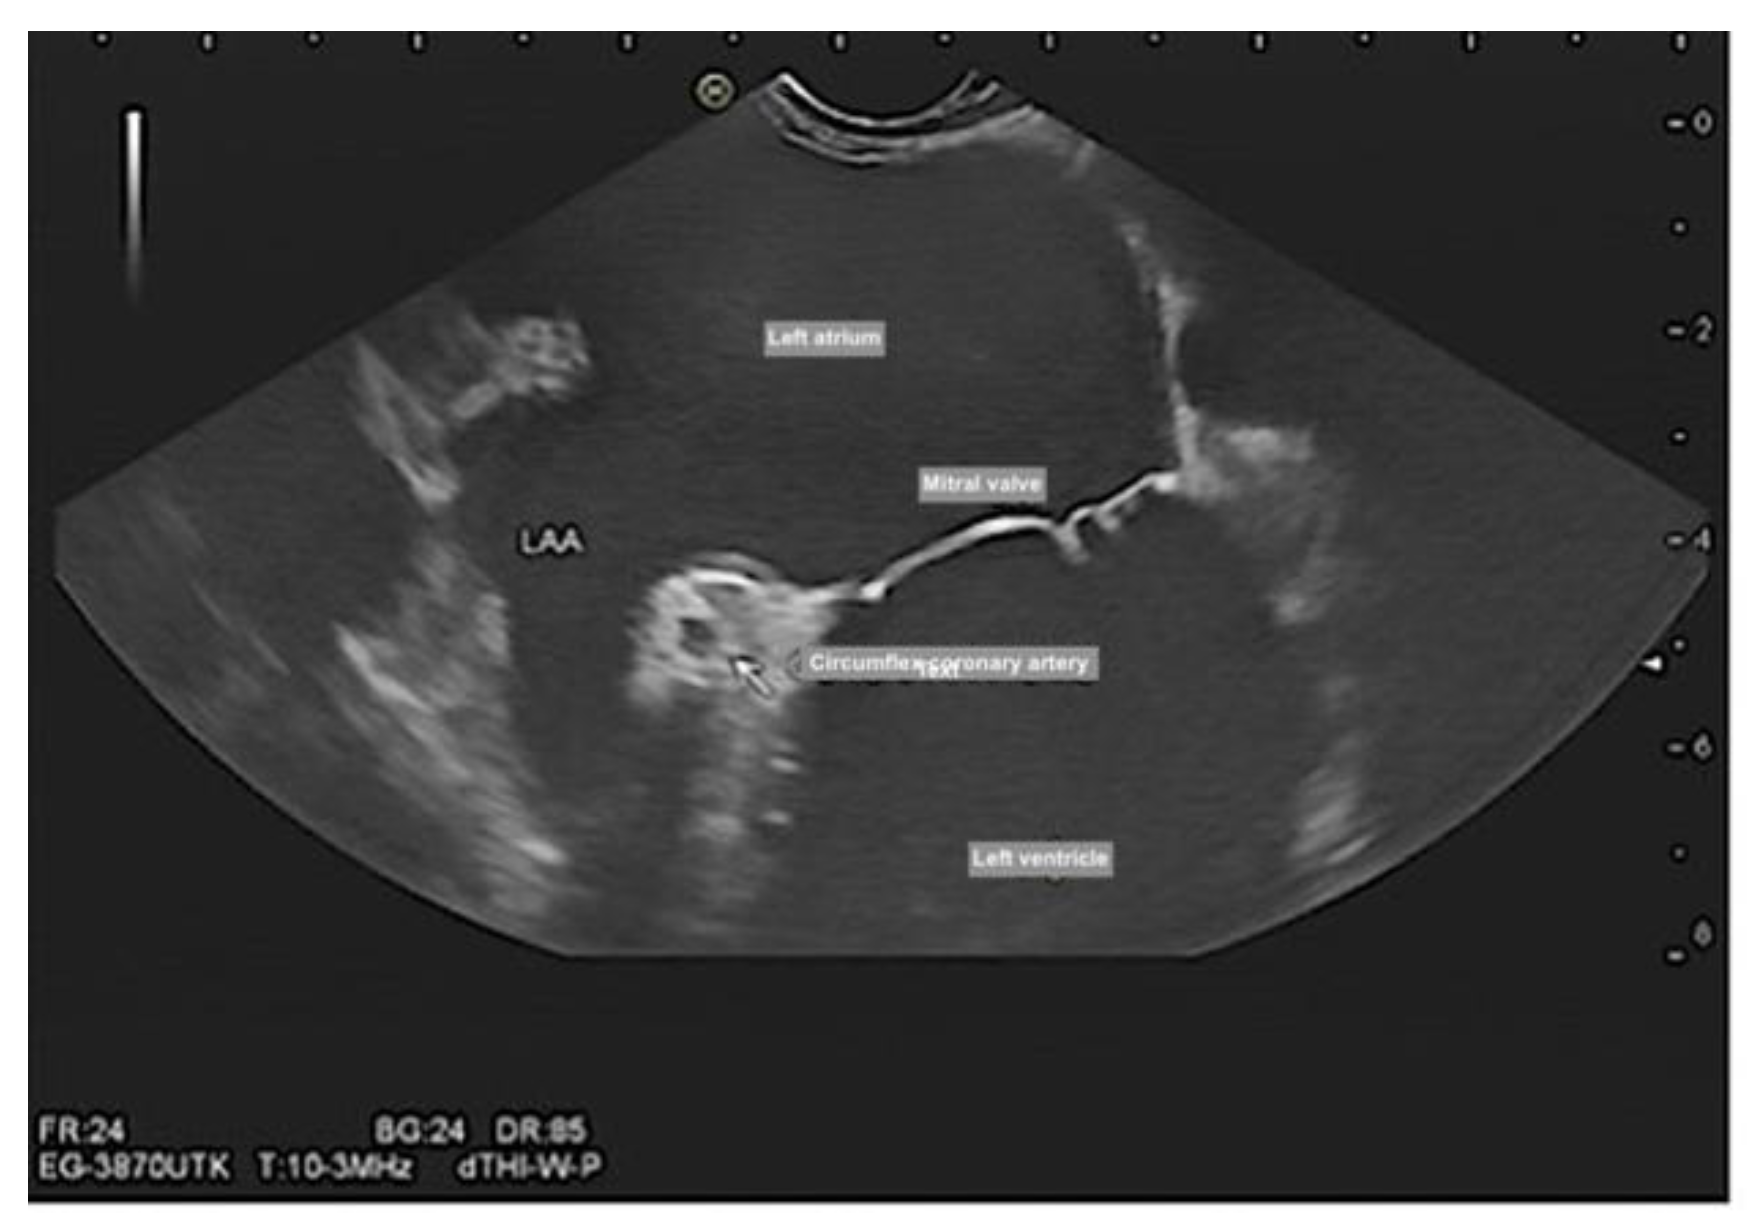

Mitral valve morphology, function, vegetation [14] and Mitral clip (Figure 4, and Videos 3–5). Mitral clip is a catheter-based edge-to-edge mitral valve repair for treating symptomatic functional mitral regurgitation (MR) in patients who are at high/prohibitive surgical risk.

Figure 4. Endosonographic ultrasound demonstrated the morphology of the mitral valve, circumflex artery, and left atrial appendage.

Preprints 79537 g004